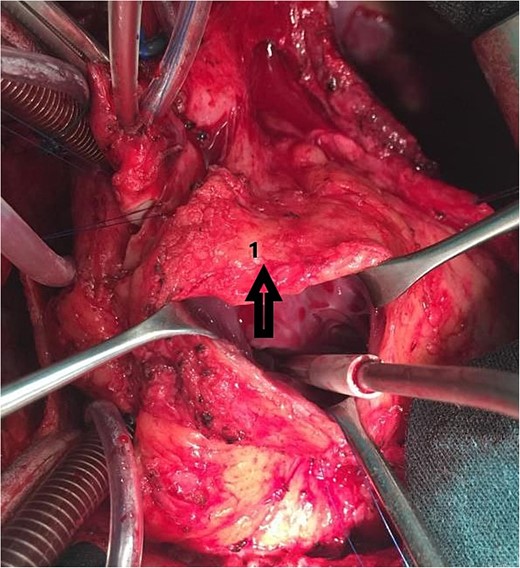

An 11-year-old girl was referred to our hospital with a main complaint of progressive exertional dyspnea. She had undergone surgical repair of SAS 6 years ago. Transthoracic echocardiogram (TTE) revealed the following findings: severe left ventricular hypertrophy, tunnel-like fibromembranous subaortic stenosis with a length of 10 mm, a peak gradient (PG) across the LVOT of 170 mmHg, and mild aortic regurgitation. Based on these findings, the patient was scheduled for elective surgical repair with a possible indication for MKO. The operation was performed via median sternotomy with great caution to avoid inadvertent rupture of any cardiac cavity due to heavy adhesions from the previous operation. The aorta was cannulated just below the takeoff of the innominate artery. Bicaval cannulation was performed to provide a bloodless field. Aortic cross-clamping was applied, and antegrade cold blood cardioplegic solution was administered via a catheter placed in the ascending aorta. The ascending aorta was opened transversely 1 cm above the sinotubular junction (Fig. 1). The aortic valve leaflets were examined carefully to confirm that the aortic valve could be preserved. LVOT was examined thoroughly, and it was clear that the stenosis in the subaortic area was so complex that simple resection through the aortic valve orifice would not be sufficient. The right ventricular outflow tract was opened transversely below the pulmonary valve. The conal papillary muscle was identified (Fig. 2). A right-angle instrument was introduced through the aortic orifice into the interventricular septum, and the tip of the instrument was used to perforate the conal septum to the left of the conal papillary muscle to prevent damage to the conduction system; the septal incision was completed with great caution to avoid damage to the aortic cusps and to extend the incision downward as necessary to completely relieve the stenotic subaortic area (Fig. 3). Interrupted 5/0 Prolene sutures were placed circumferentially around the septal incision to close the interventricular septal defect using a bovine pericardial patch to provide adequate widening of LVOT (Fig. 4). The right ventriculotomy was closed with a second bovine pericardial patch to avoid any possible obstruction of the right ventricular outflow tract (Fig. 5). The remainder of the operation was completed uneventfully. After 6 hours of mechanical ventilation, the patient was extubated, and she convalesced well postoperatively. TTE showed excellent results of the operation with PG across LVOT of 20 mmHg. On 1 year follow-up, the patient was asymptomatic and in very good general condition, and TTE findings confirmed the excellent result.

Intraoperative image showing the opened aorta. The arrow points to the aortotomy, and the star points to the stenotic left ventricular outflow tract through the aortic orifice.